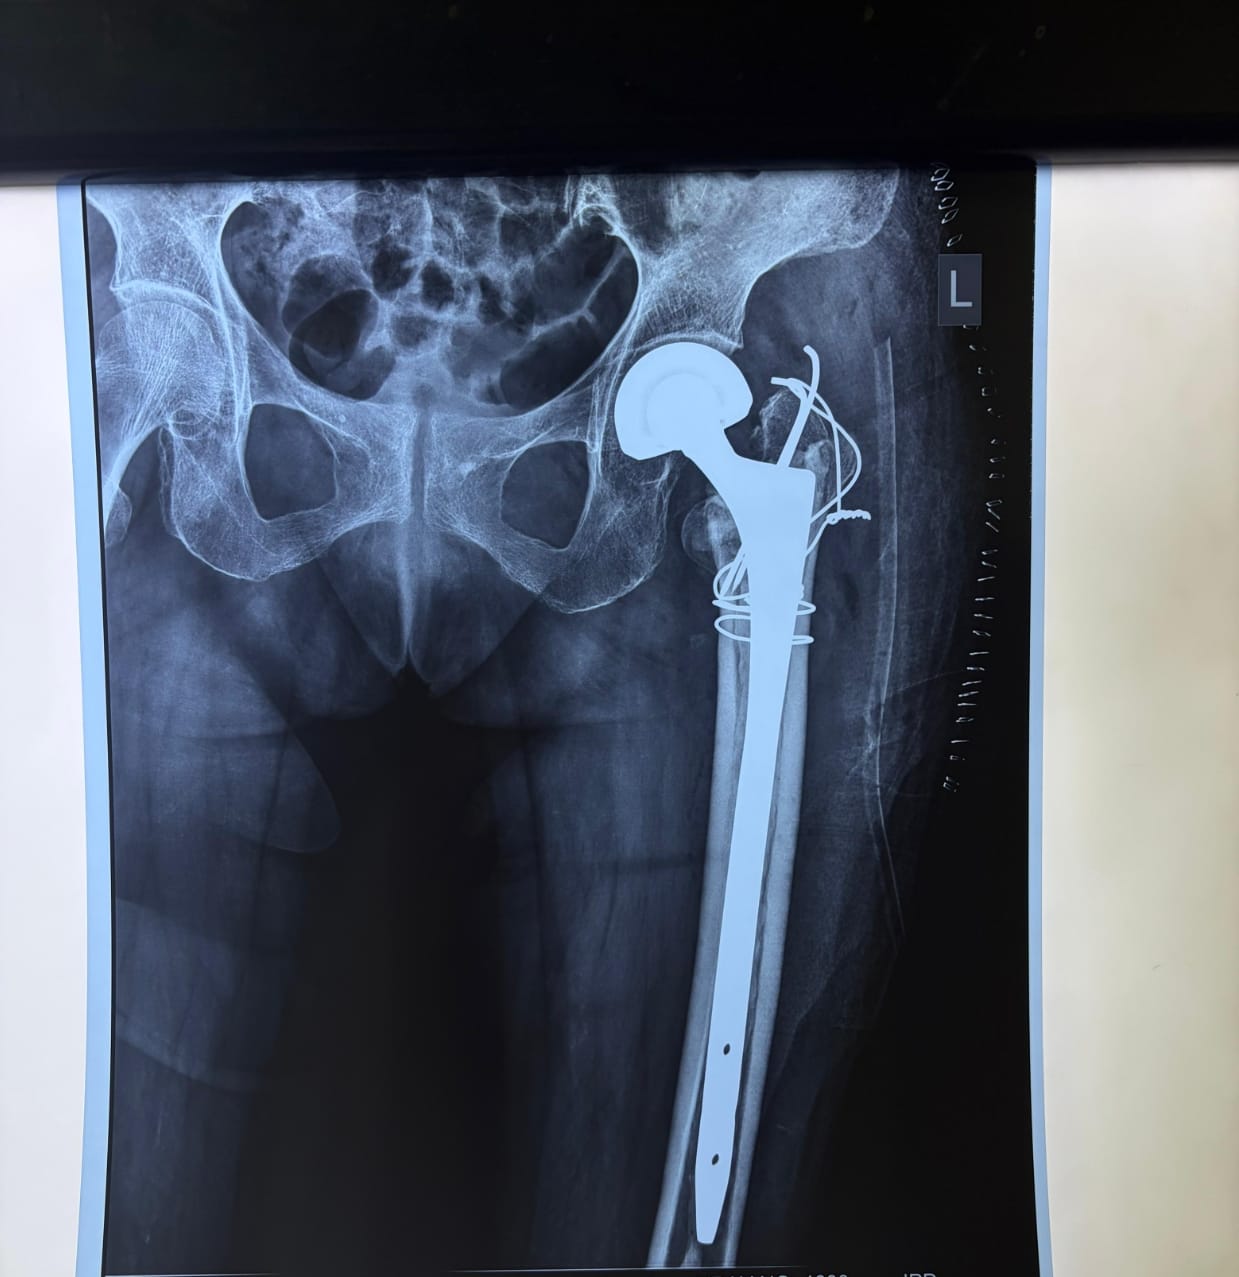

‘लंबे स्टेम वाले मॉड्यूलर बाइपोलर कृत्रिम कूल्हा प्रत्यारोपण,

डॉ. तरुण सिंह ने बताया कि अधिक उम्र में इस प्रकार के कूल्हे के फ्रैक्चर का सामान्य रूप से जुड़ पाना बेहद कठिन होता है। ऐसे मरीजों को कई महीनों तक बिस्तर पर रहना पड़ता है, जिससे संक्रमण, कमजोरी और अन्य बीमारियों का खतरा बढ़ जाता है। मरीज की स्थिति को देखते हुए विभागाध्यक्ष डॉ. बेन के मार्गदर्शन में चिकित्सकों की टीम ने उन्नत तकनीक का उपयोग करते हुए लंबे स्टेम वाले मॉड्यूलर बाइपोलर कृत्रिम कूल्हा प्रत्यारोपण, टीबीडब्ल्यू तकनीक तथा हड्डी को मजबूती देने के लिए एन्क्लेज वायरिंग की सहायता से सफल सर्जरी की।